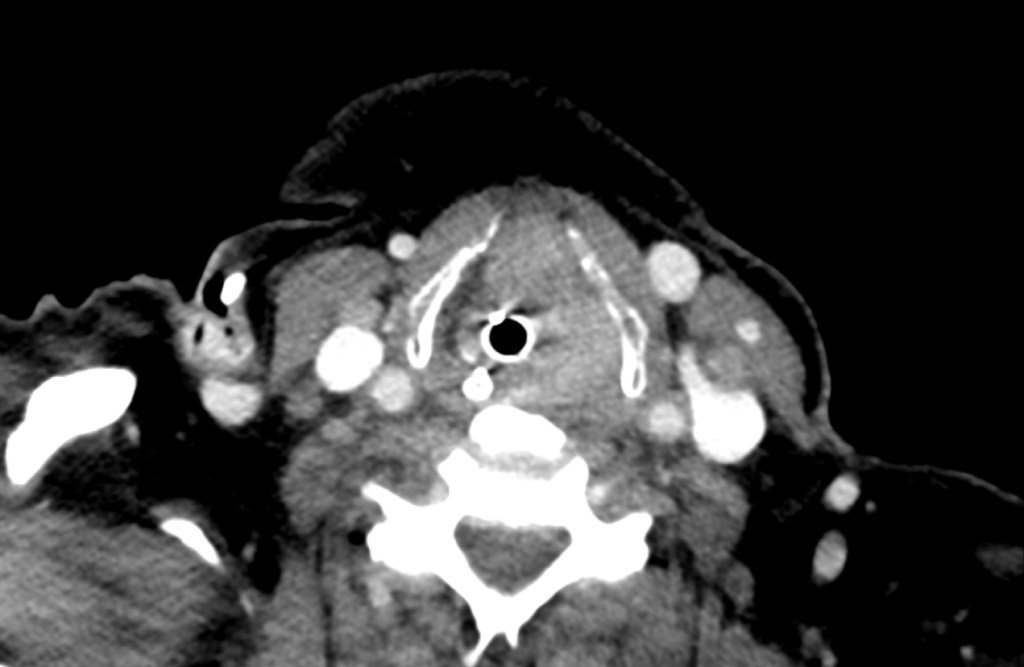

Unexpected Difficult View

This patient had an unexpected supraglottic mass, making laryngoscopy difficult. The epiglottis is swollen and surrounded by inflamed and friable tissues.

This patient was intubated successfully by the team and the CT scan image is shown below.